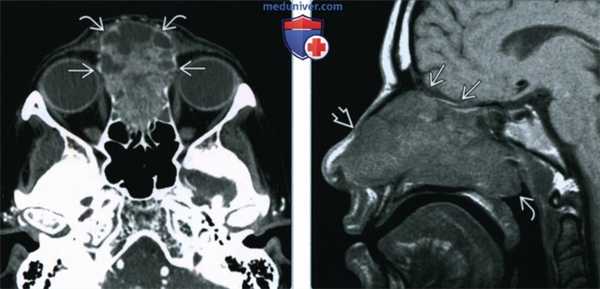

(Слева) При аксиальной КТ с КУ визуализируется большая аденокарцинома, неравномерно накапливающая контраст, и заполняющая верхние отделы полости носа и решетчатые пазухи. Опухоль прорастает кпереди в мягкие ткани спинки носа и разрушает глазничную пластинку с обеих сторон.

(Справа) При сагиттальной МРТ Т1 ВИ визуализируется крупная аденокарцинома, заполняющая полость носа и распространяющаяся в носоглотку. Опухоль не прорастает через основание черепа, но распространяется в подкожную клетчатку спинки носа.